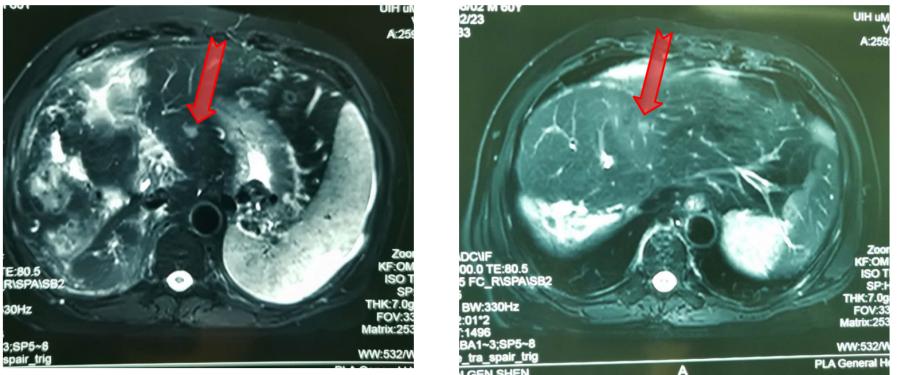

2017年4月15日复查,疾病进展(图3)。出现门腔静脉间淋巴结转移(图4)。

图3.术后7个月复查腹部MR

图4.术后7个月复查腹部MR 门腔静脉间淋巴结转移

2017年5月再次行一次TACE治疗。6月行射波刀治疗,8 Gy/次,共6次。放疗后淋巴结及门静脉癌栓退缩,但是右肝又出现了新的病灶(图5)。

图5. 放疗后腹部MR